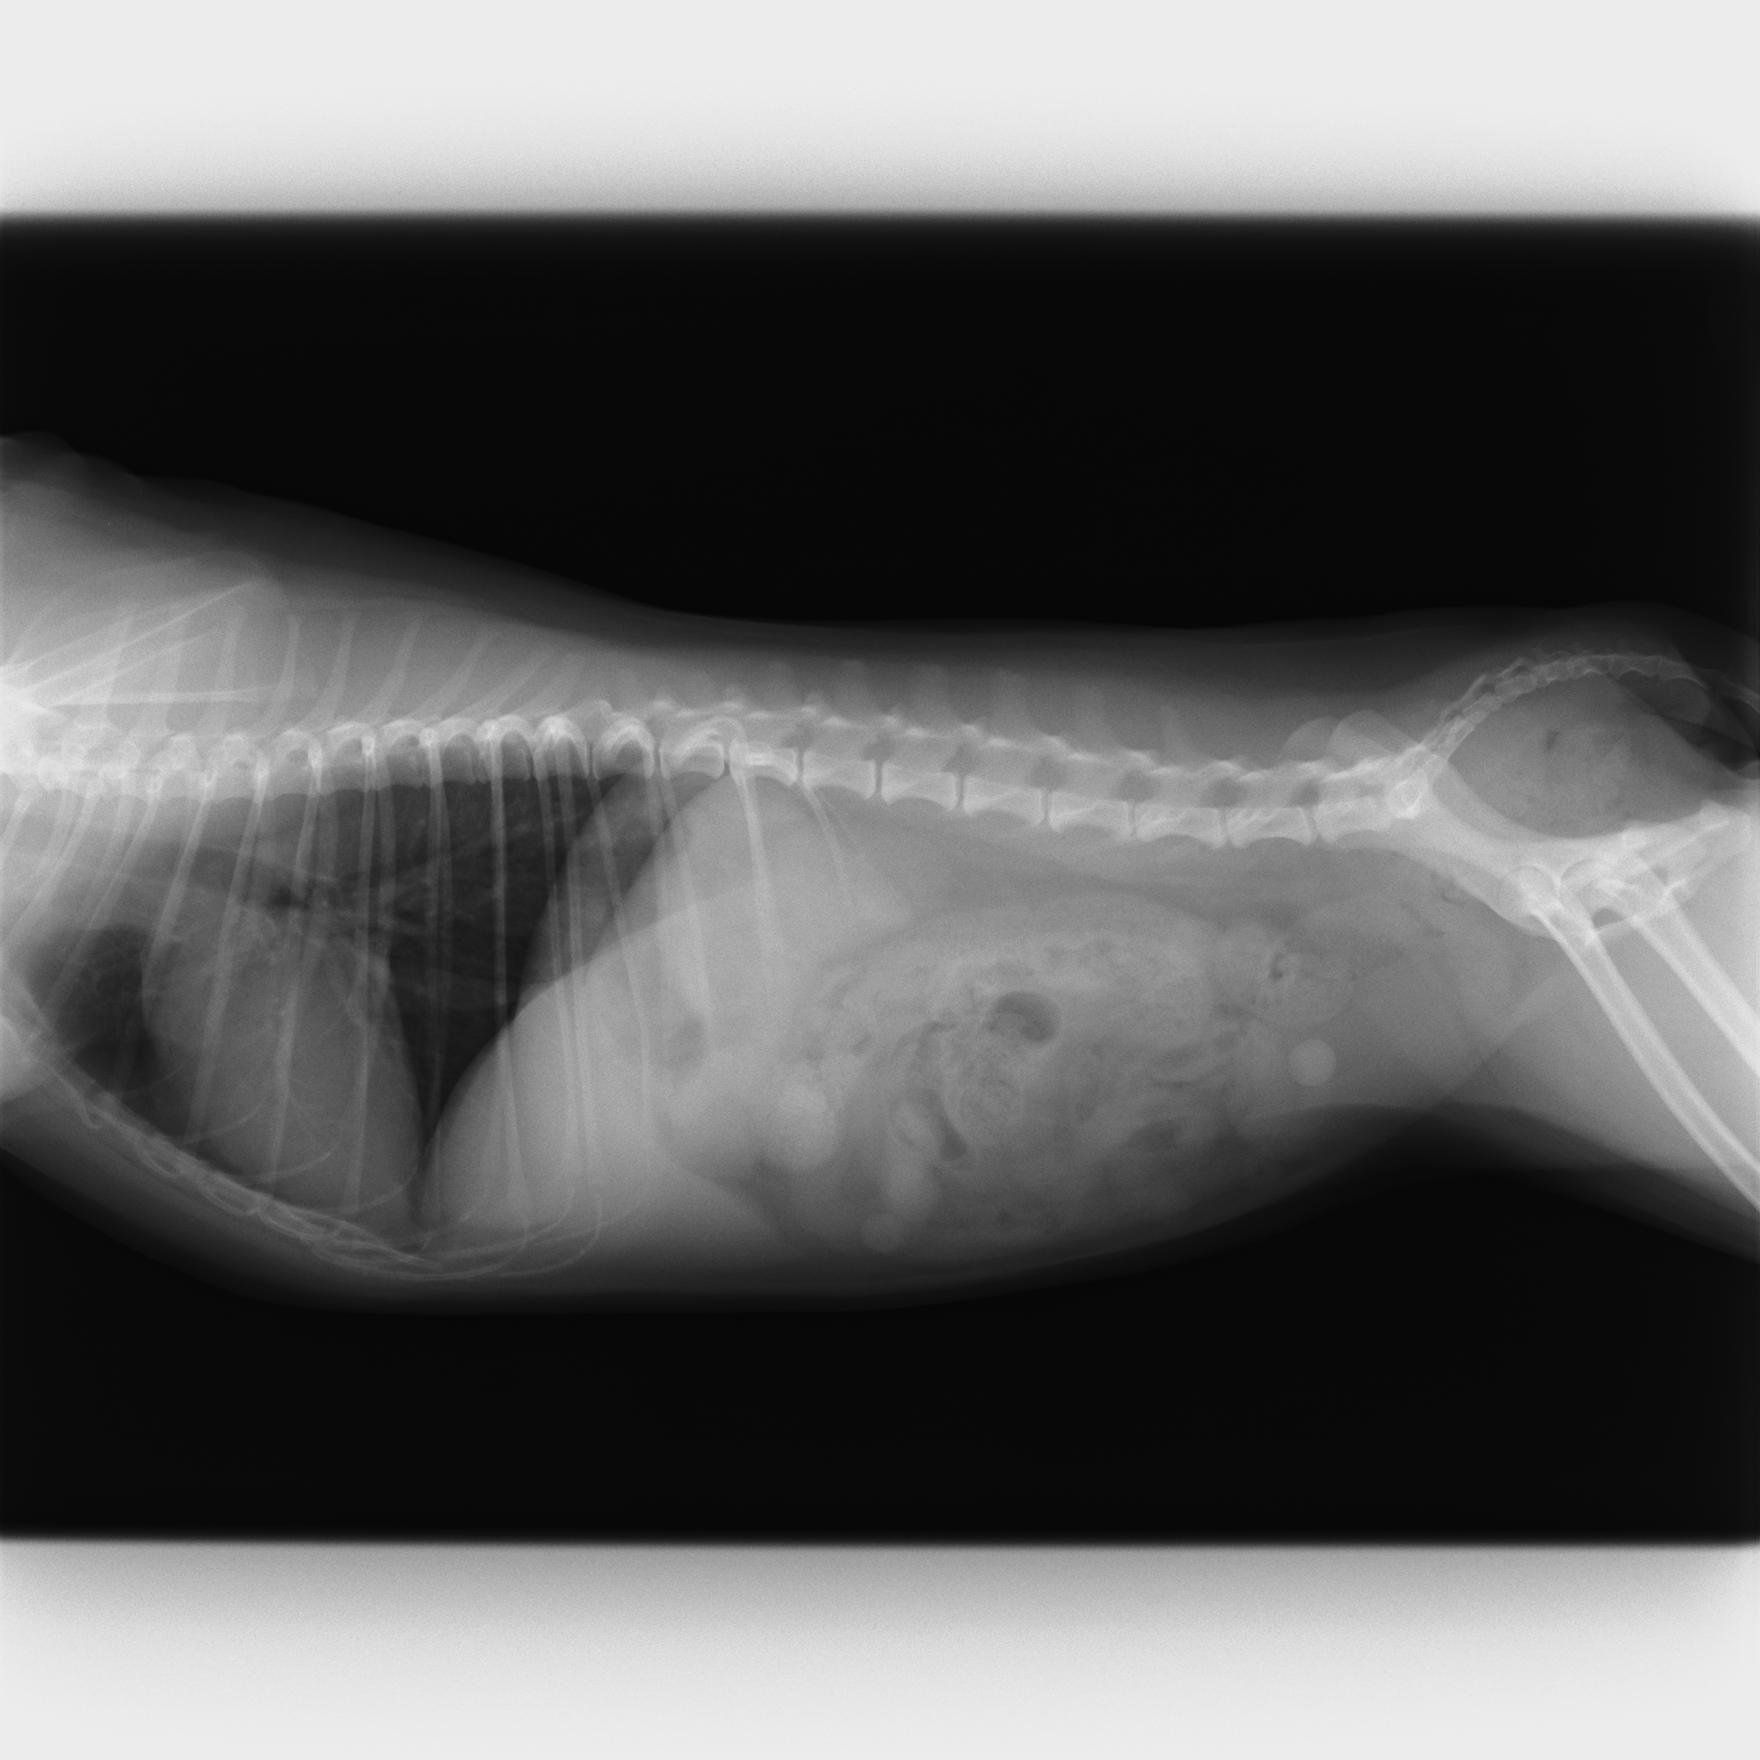

石になる前に流れてしまう……メスの尿石症

尿石症(にょうせきしょう)とは、オシッコの通り道に石ができて詰まってしまう病気です。尿に含まれるミネラルが結晶化し、尿道で詰まるとさまざまな症状を引き起こします。オスがよくなる病気として知られていますが、メスはオスより尿道が短いので、結晶ができてもすぐに砂状になって排出されてしまうことが多いため、尿石症であると気づきにくい傾向があります。